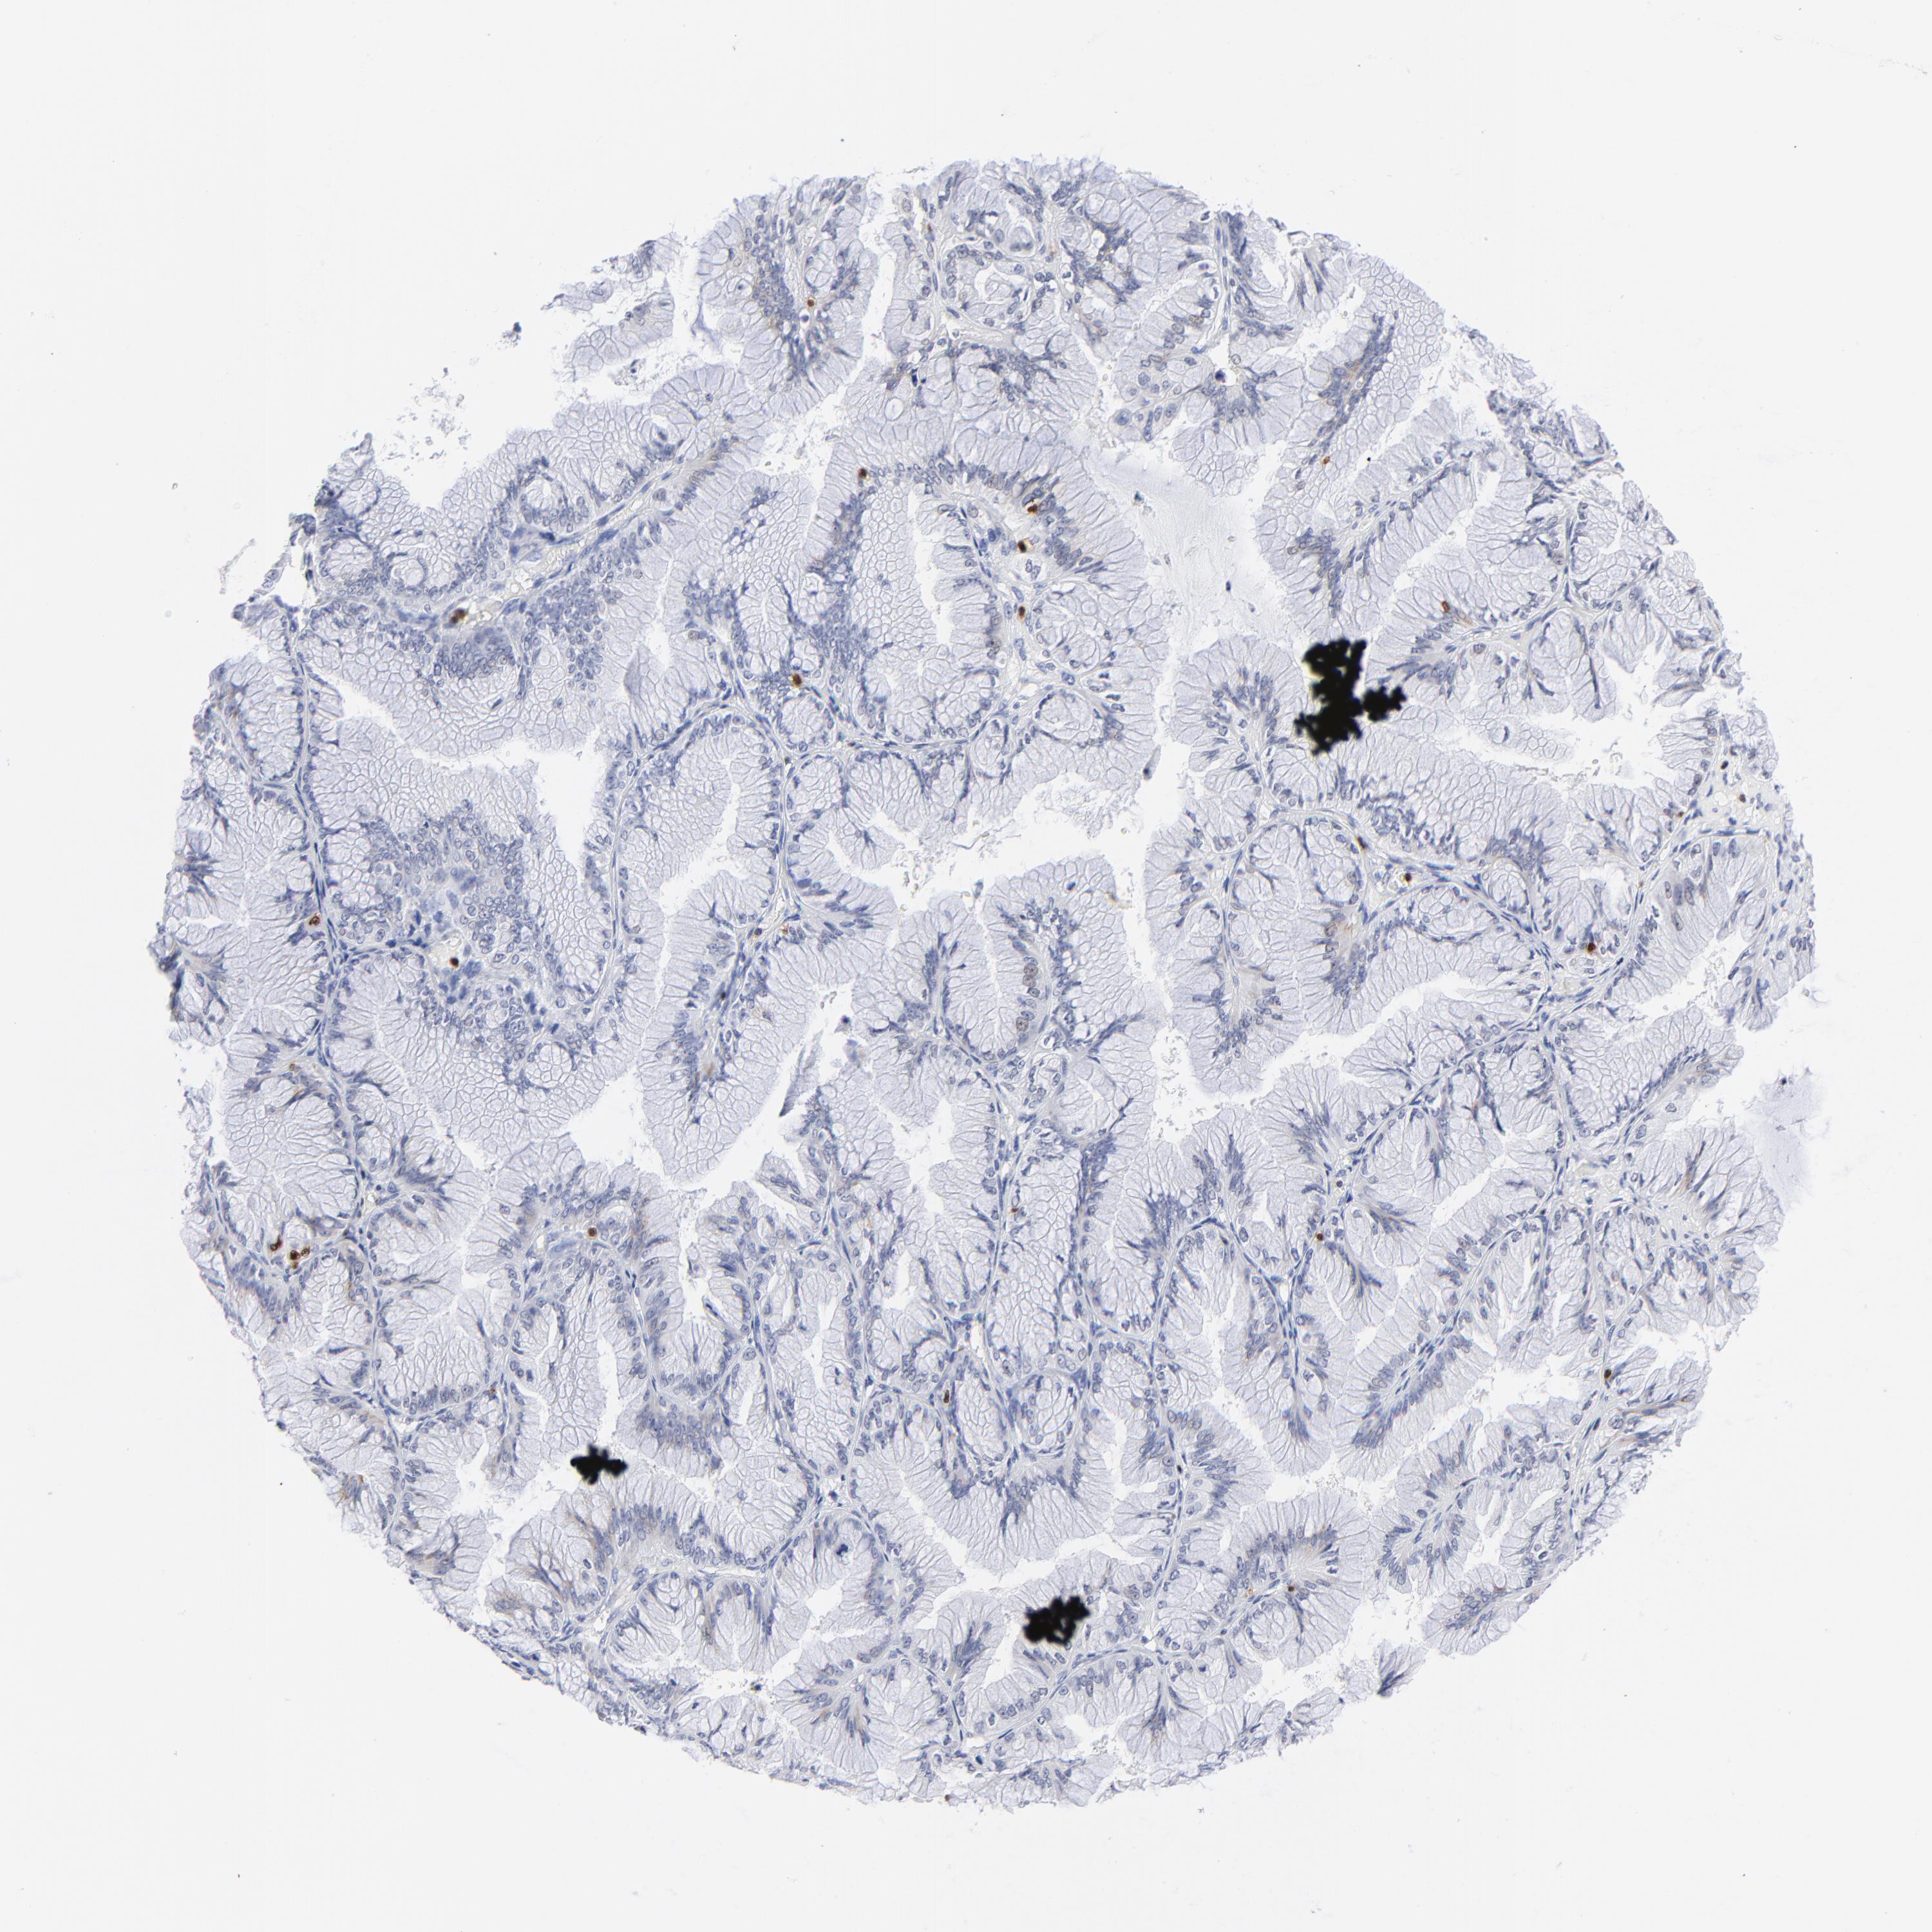

OVARIAN CANCER - Protein expressioni

A mouse-over function shows sample information and annotation data. Click on an image to view it in a full screen mode. Samples can be filtered based on level of antibody staining by selecting one or several of the following categories: high, medium, low and not detected. The assay and annotation is described here.

Note that samples used for immunohistochemistry by the Human Protein Atlas do not correspond to samples in the TCGA dataset.

Antibody stainingi

Antibody staining in the annotated cell types in the current human tissue is reported as not detected, low, medium, or high, based on conventional immunohistochemistry profiling in selected tissues. This score is based on the combination of the staining intensity and fraction of stained cells.

Each image is clickable and will lead to virtual microscopy that enables deeper exploration of all samples and also displays staining intensity scores, fraction scores and subcellular localization as well as patient and tissue information for each sample.

Antibody CAB002625

Cystadenocarcinoma, mucinous, NOS

Carcinoma, endometroid

Cystadenocarcinoma, serous, NOS